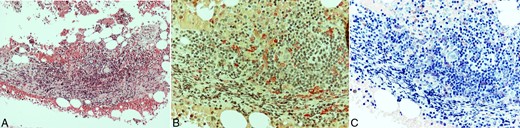

He underwent a complete L4 and a partial L3 laminectomy plus posterior lumbar fusion with pedicle screws from L2 to S1 vertebrae. Remarkable vertebral softness was documented during surgery. Postoperatively, bone mineral density was measured and showed osteoporotic findings. The postoperative course was uneventful. Further investigation found abnormally elevated serum tryptase levels: 25.2 μg/l (normal values <11.4 μg/l). Α bone marrow biopsy was performed and showed nests of spindle-shaped or ovoid cells with atypical morphology, eosinophilic cytoplasm and irregular or elongated nuclei. Ηistochemical staining with chloroacetate esterase and Giemsa and immunohistochemical staining with tryptase and CD117 demonstrated similar cell aggregates (Fig. 2). A bone marrow sample tested by polymerase chain reaction was found positive for the D816V somatic mutation in the exon 17 of the c-KIT gene.

Bone marrow biopsy. Hematoxylin and eosin (H&E) stain showing nodular infiltration by lymphocytes and atypical mast cells, forming loose aggregates (A), highlighted by chloroacetate esterase (B), and Giemsa histochemical stains (C). A, H&E (×200); B, Chloroacetate esterase (×400); C, Giemsa (×400).